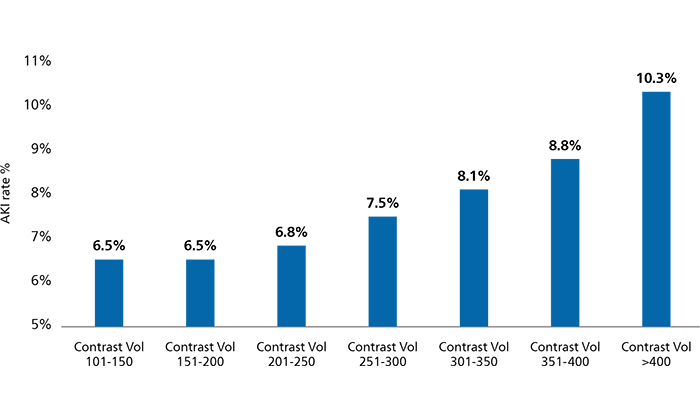

Every incremental 75ml of contrast used increased the risk of AKI by 42%15

1,349,612 patients who underwent PCI (CathPCI Registry)15

Contrast volume

Contrast volume is a key risk factor for CI-AKI and matters the most in the highest-risk patient. The incremental use of contrast beyond the Maximal Allowable Contrast Dose (MACD) is associated with an increased risk of CI-AKI.14

MACD = Contrast volume/eGFR ratio ≤ 1.

MACD Ratio and CI-AKI. Calculated ratios of contrast volume to the predicted Maximal Allowable Contrast Dose (MACD) are plotted by the crude (orange bars) and risk-adjusted (black diamonds) rates of contrast-induced acute kidney injury (CI-AKI).